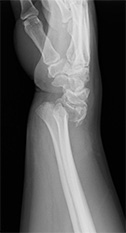

橈骨遠位端骨折(手首の骨折)

転倒時に手をついて生じることが多い骨折です。

ずれが小さい場合は保存療法(ギブス固定)も可能です、ずれが大きい場合や早期のギブス除去、社会復帰を希望される場合に手術を行っております。

• 画像:橈骨遠位端骨折

(術前)